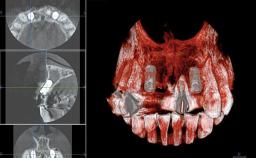

Replacement of Teeth 12 and 13 with Tissue-Level Implants

In 2001, a 48-year-old woman presented at a dental clinic with a failing fixed partial denture spanning from teeth 13 to 21. She was experiencing pain upon function, tenderness to palpation facial to tooth 13, and severe mobility of the prosthesis. Radiographic and clinical assessment revealed a subcrestal fracture of tooth 13, making its restoration unlikely. It was determined by the clinician that the tooth needed to be extracted prior to proceeding any further with dental care. After the extraction, the patient lost confidence in the progression of her treatment and sought consultation at the Center for Implant Dentistry. At her consultation visit in our clinic, an extra- and intraoral clinical examination revealed a medium lip line at full smile and an edentulous area spanning from 13 to 12 with both vertical and horizontal deficits in hard and soft tissue.